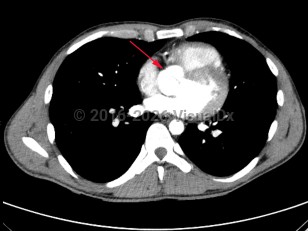

Congenitally abnormal aortic valve with only two functional valve cusps, usually due to fusion of two of the cusps. This is associated with valvular stenosis and/or insufficiency, as well as abnormalities of the aorta including aneurysms and coarctation. It may occur alone or with other cardiovascular abnormalities such as ventricular septal defect, patent ductus arteriosus, and sinus of Valsalva aneurysm.

Common signs and symptoms include chest pain, decreased exercise tolerance, dyspnea, heart murmur, palpitations, syncope, and aortic regurgitation, or patients may remain asymptomatic for a long time. Infective endocarditis, aortic dilation, and aortic dissection are serious complications. A life-threatening association with symptomatic aortic stenosis puts the patient at risk of sudden death.